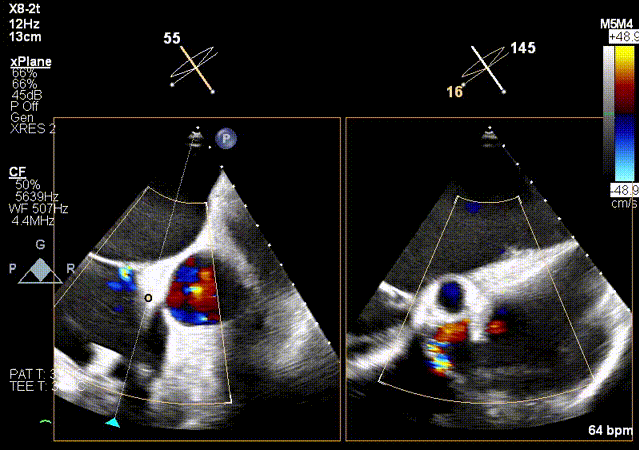

5.关闭夹子后超声评估。

术前

植入第一枚夹子后

1.反流效果:重度5+下降至轻度1+。

术后